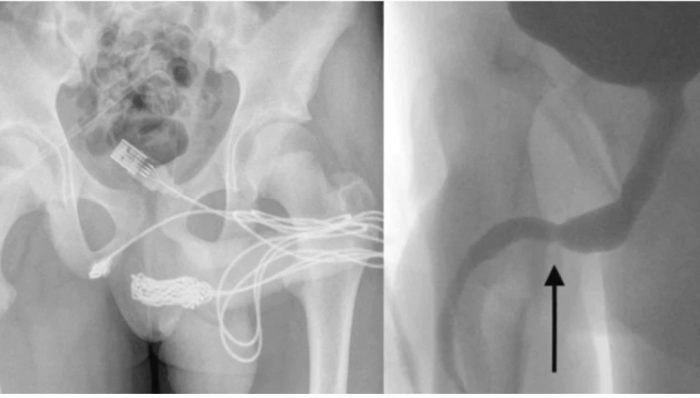

डॉक्टरों को यू उसके प्राइवेट पार्ट में से यूएसबी निकालने के लिए ऑपरेशन करना पड़ा। ये खबर आप हिमाचली खबर में पढ़ रहे हैं। युवक के पेनीस के पास ही एक बड़ा चीरा लगाने के बाद केवल को निकाला जा सका। इसके लिए डॉक्टरों ने पहले युवक के प्राइवेट पार्ट का सिटी स्कैन किया जिसमें उन्हें यूएसबी केबल अंदर फंसे हुए नजर आए डॉक्टर के पास चीरा करके केबल को निकालने के अलावा कोई दूसरा रास्ता नहीं था इसलिए ऑपरेशन करना पड़ा। ऑपरेशन सफल होने के बाद डॉक्टर ने बताया कि युवक को छुट्टी दे दी गई है और उन्हें कोई अंदरूनी चोट तो नजर नहीं आई लेकिन दो सप्ताह बाद वापस युवक को स्कैनिंग के लिए आना पड़ेगा।